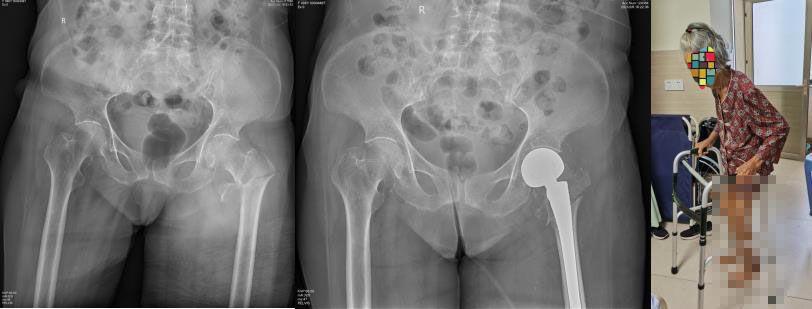

老年粗隆部骨折,行半髋关节置换重建,实现早期离床下地活动,避免长期卧床造成的各类并发症。图为96岁的患者,术后第一天即可离床活动。